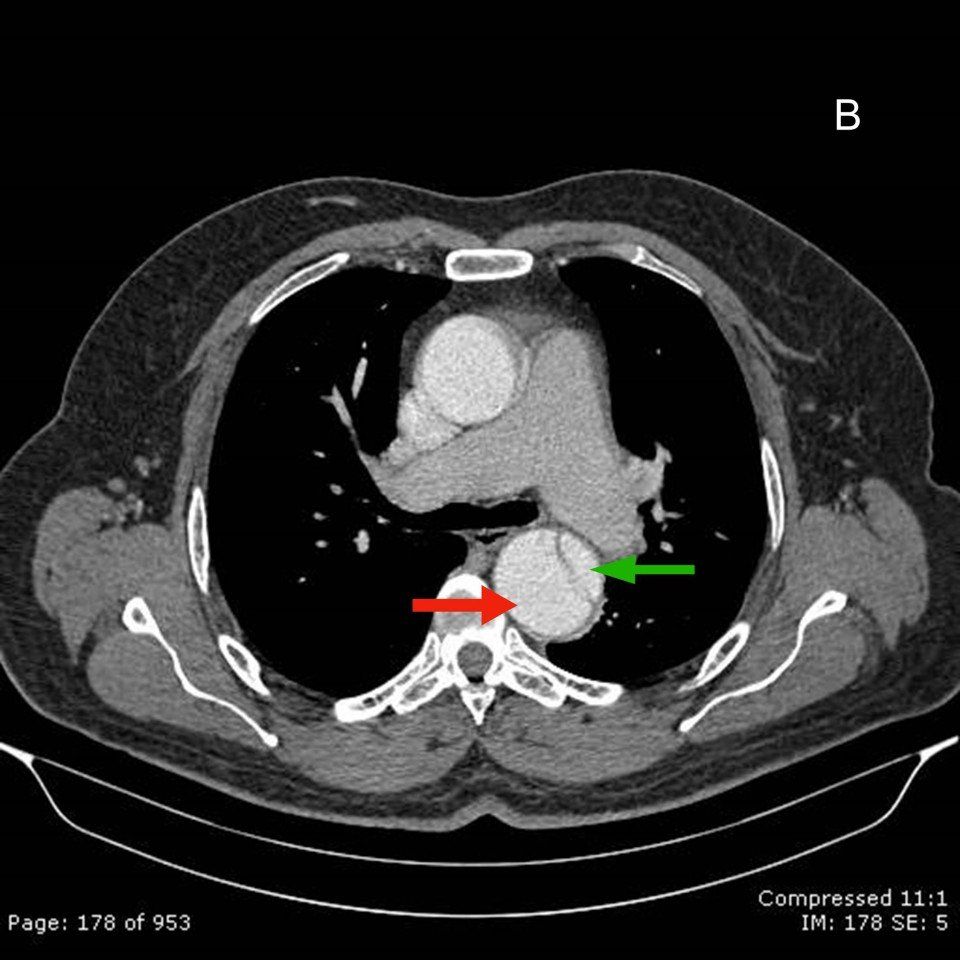

O diagnóstico de dissecção baseia-se na identificação do flap intimal, que se apresenta como uma fina membrana separando a luz falsa da verdadeira. A sensibilidade e a especificidade da angiotomografia em visualizar o flap intimal são superiores a 95%.

B. Definição das luzes verdadeiras e falsa:

Alguns aspectos ajudam a definir as luzes verdadeira e falsa:

- A luz falsa com frequência tem área transversal maior devido ao fluxo lento.

- A luz verdeira encontra-se comprimida em 80% dos caos.

- A falsa luz tem maior propensão à trombose.

- O fluxo sanguíneo lento leva a retardo na opacificação da luz falsa no inicio da hélice, com opacificação prolongada em direção ao término.

- Quando uma luz envolve a outra, a luz interna invariavelmente é a verdadeira.

- Calcificações na parede da aorta não permitem a separação das duas camadas; assim, sua presença indica a intima da luz verdadeira, em se tratando de dissecção aguda.

- A eventual calcificação da intima dissecada encontra-se na face voltada à luz verdadeira.

- Sinal do bico: ângulo agudo formado na junção da intima dissecada e a parede da falsa luz.